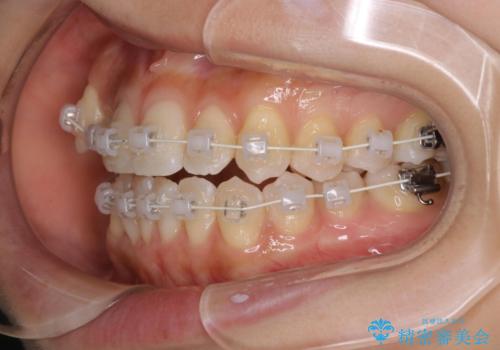

- 矯正装置

- 審美装置

- 八重歯と叢生を主訴に来院されました。なるべく健康な歯を残したいという患者様の希望から、右側上下4番抜歯をしてワイヤー矯正する治療計画を立てました。

なるべく健康な歯を残したいという患者様の希望から、右側上下4番抜歯をして矯正しました。片側抜歯だったため、正中がズレないように気をつけながら治療を行いました。